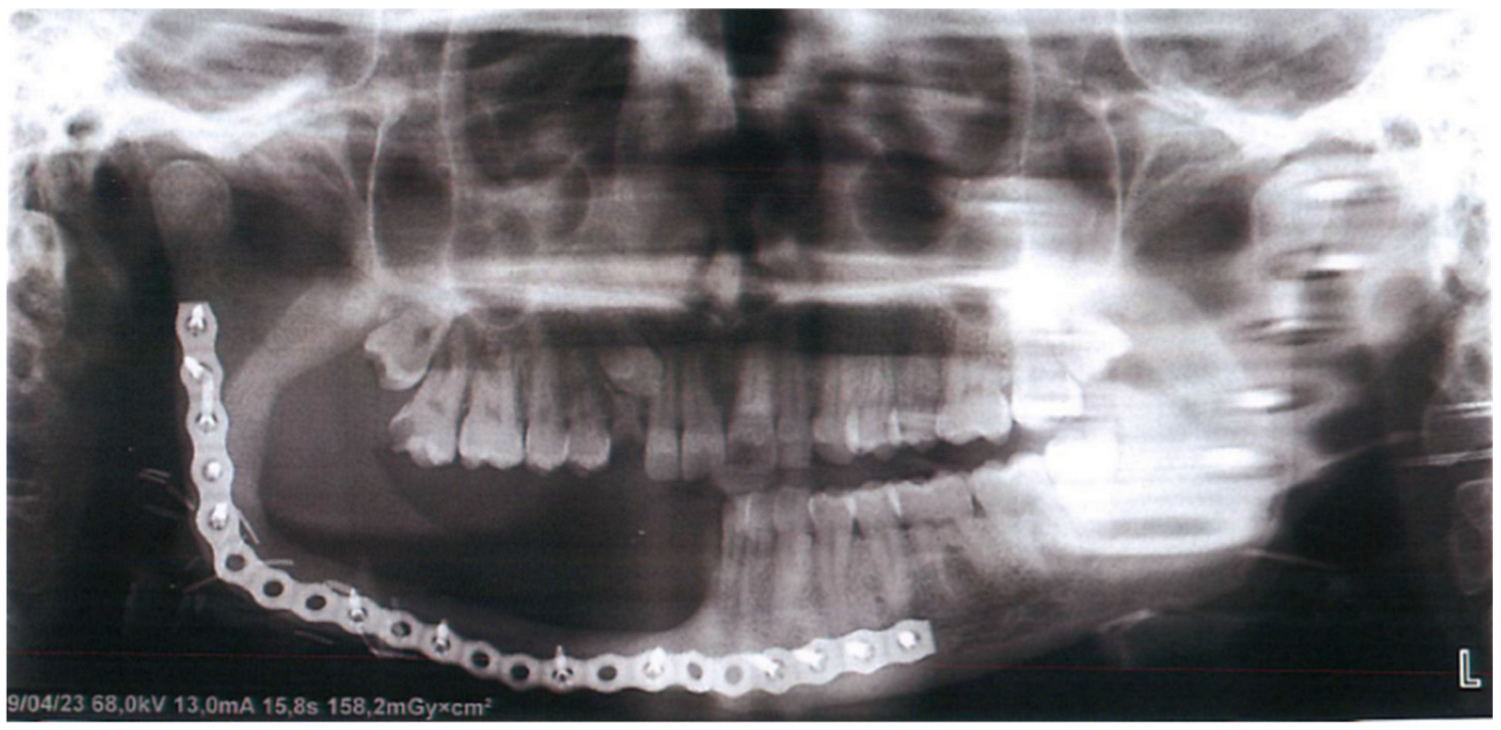

| 2021 | Lesion was resected and reconstructed with fibula graft |

| 2023 | Surgery of 4 implants in the jaw |

| 2023 | Removal of 2 dental implants |